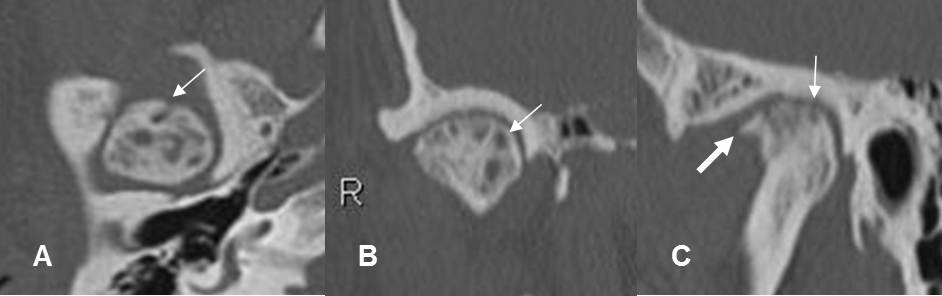

Fig 18 A. Cambios degenerativos.

A: TAC axial, B: TAC reconstrucción coronal y C: TAC reconstrucción sagital. Cambios degenerativos en la ATM, con disminución del espacio articular, formación de osteofito (Flecha gruesa) y lesiones osteocondrales (Flechas delgadas).